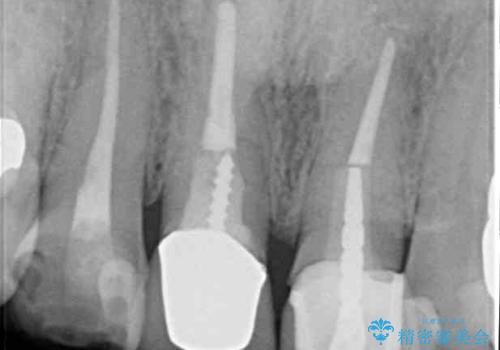

検査の結果、右前歯の歯根が縦に破折していることが分かりました。

破折している歯は抜歯をし、歯肉が窪んでしまうので、傷口の治りを待って、歯肉移植を行うこととしました。